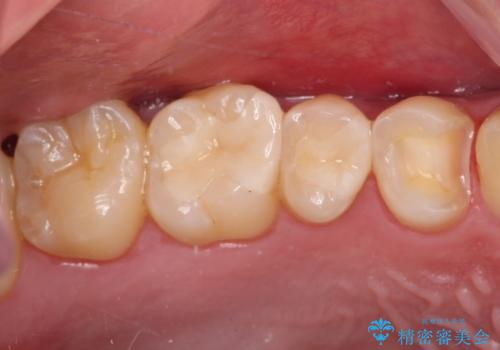

詰め物が外れた セラミックインレー修復

- 以前治療した詰め物が外れてしまい、冷たいものがしみることを主訴として来院された患者様です。

むし歯がないことを確認し、セラミックインレーにて修復するととしました。

適合の良いセラミックインレーの装着により、冷たいものがしみる症状はなくなりました。